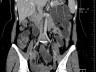

Case of the Week 25 2016 *39-year-old female with abdominal pain and vomiting. What is the most likely diagnosis? Answer Answer: Small bowel obstruction caused by intussusception produced by an ileal lipoma. Kategori:Cases Önceki yazı Case of the Week 21 2016 Sonraki yazı Case of the Week 26 2016